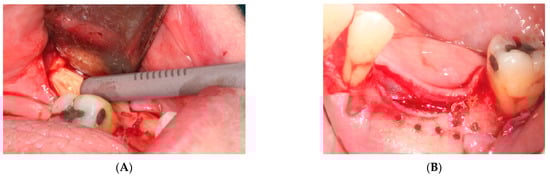

- First surgery: Local anesthesia Articaine 4% with epinephrine (1:100,000) was administered. An intrasulcular incision was made from the mesial of 3.3 to the distal of 3.7, continuing along the anterior border of the external ramus of the mandible. Periosteal incisions were made to mobilize the vestibular flap and the upper fibers of the mylohyoid muscle were disinserted to passivate the lingual flap and thus obtain a tension-free closure (Figure 3). We then checked the position of the mesh and proceeded to collect bone from the ascending branch using the bone scraper (Micross®, Selecdent, Barcelona, Spain) (Figure 4A). Cortical perforations were made to promote bleeding (Figure 4B). We mixed the autologous bone with the xenograft (Tioss®, Sanhigia, Bujaraloz, Spain) in a 70:30 ratio, inserted it into the mesh, and the mesh was placed in the defect.